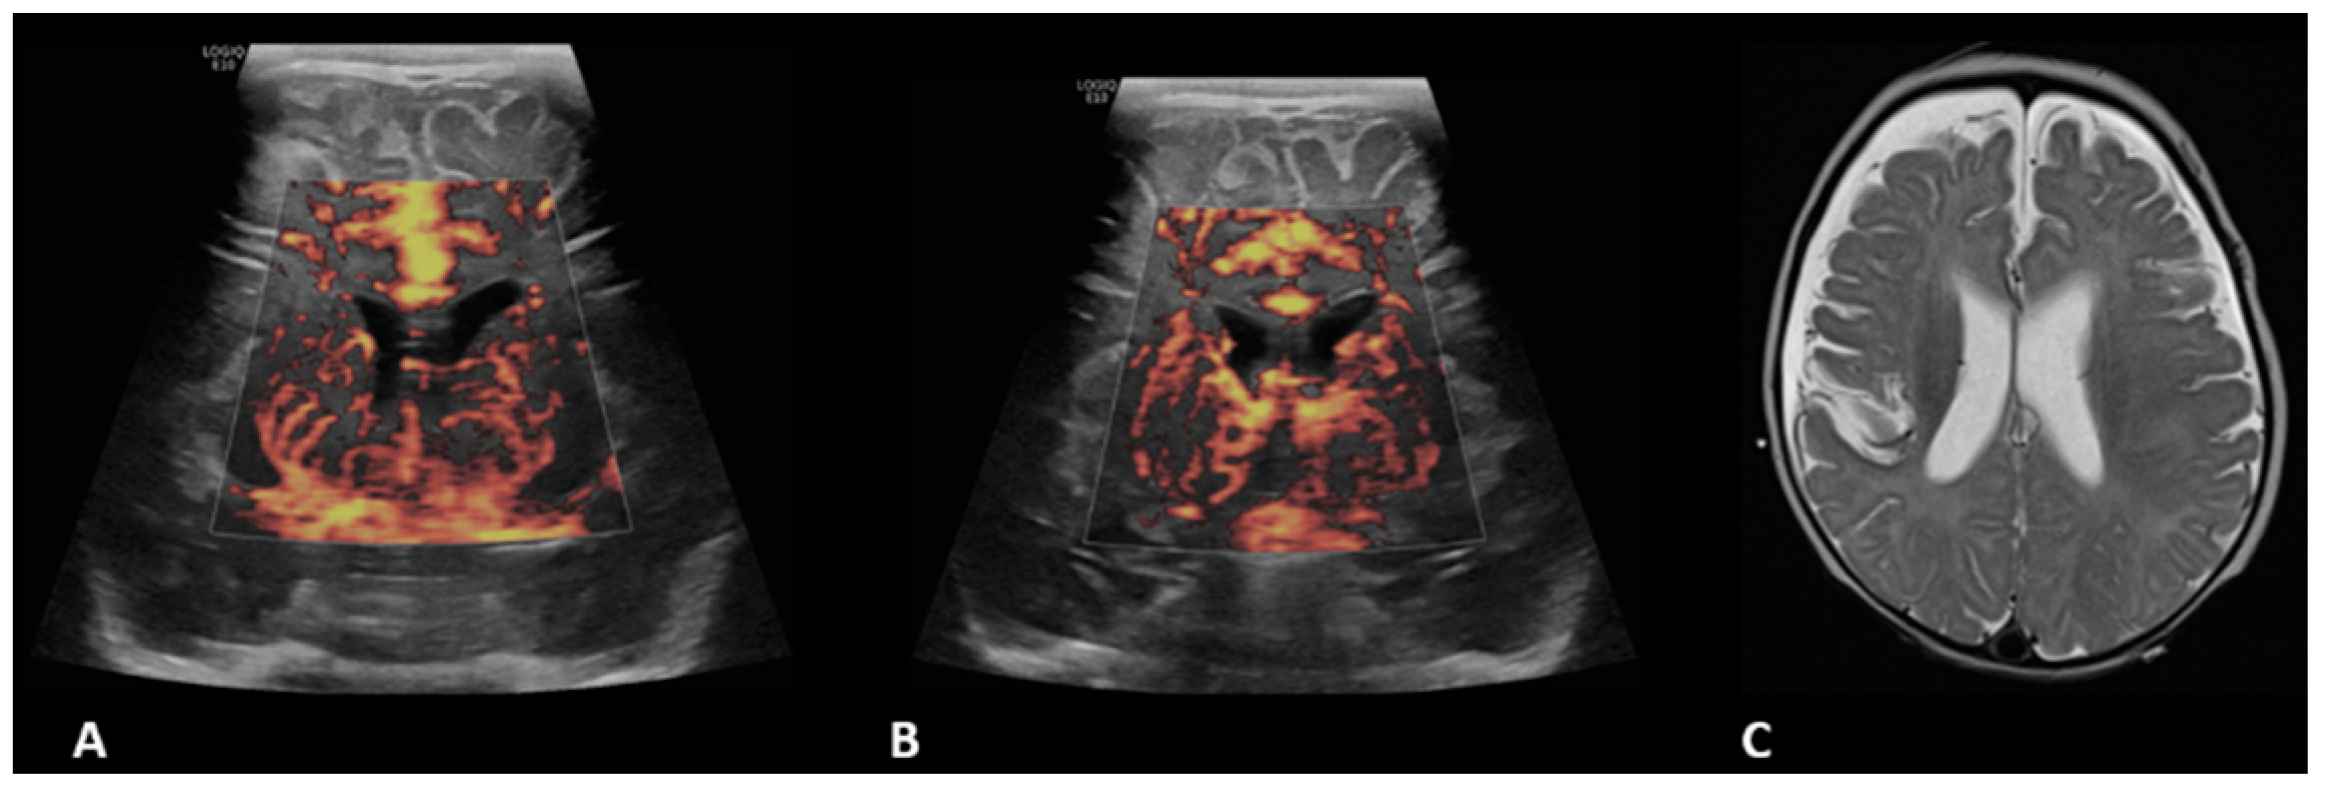

- Hwang, M.; Haddad, S.; Tierradentro-Garcia, L.O.; Alves, C.A.; Taylor, G.A.; Darge, K. Current understanding and future potential applications of cerebral microvascular imaging in infants. Br. J. Radiol. 2022, 95, 20211051. [Google Scholar] [CrossRef] [PubMed]

- Barletta, A.; Balbi, M.; Surace, A.; Caroli, A.; Radaelli, S.; Musto, F.; Saruggia, M.; Mangili, G.; Gerevini, S.; Sironi, S. Cerebral superb microvascular imaging in preterm neonates: In vivo evaluation of thalamic, striatal, and extrastriatal angioarchitecture. Neuroradiology 2021, 63, 1103–1112. [Google Scholar] [CrossRef]

- Goeral, K.; Hojreh, A.; Kasprian, G.; Klebermass-Schrehof, K.; Weber, M.; Mitter, C.; Berger, A.; Prayer, D.; Brugger, P.C.; Vergesslich-Rothschild, K.; et al. Microvessel ultrasound of neonatal brain parenchyma: Feasibility, reproducibility, and normal imaging features by superb microvascular imaging (SMI). Eur. Radiol. 2019, 29, 2127–2136. [Google Scholar] [CrossRef] [PubMed]

- Lyo, S.; Tierradentro-Garcia, L.O.; Viaene, A.N.; Hwang, M. High-resolution neurosonographic examination of the lenticulostriate vessels in neonates with hypoxic-ischemic encephalopathy. Br. J. Radiol. 2022, 95, 20211141. [Google Scholar] [CrossRef] [PubMed]